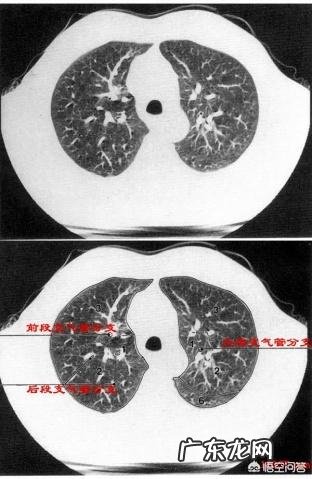

第三、肺大家都了解了,负责着人类机体的气体交换 。将新鲜的氧气带入机体内,同时将人体产生的二氧化碳排出体外 。如果肺功能衰竭,人体将面临巨大挑战 。